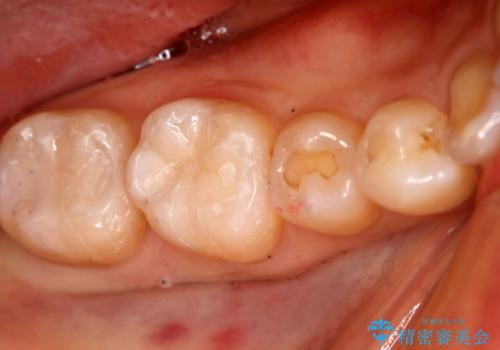

精密根管治療を行なったことで病巣は消失し、腫れや痛みは再発することなく経過は良好です。

被せ物はフルジルコニアクラウンを選択されました。